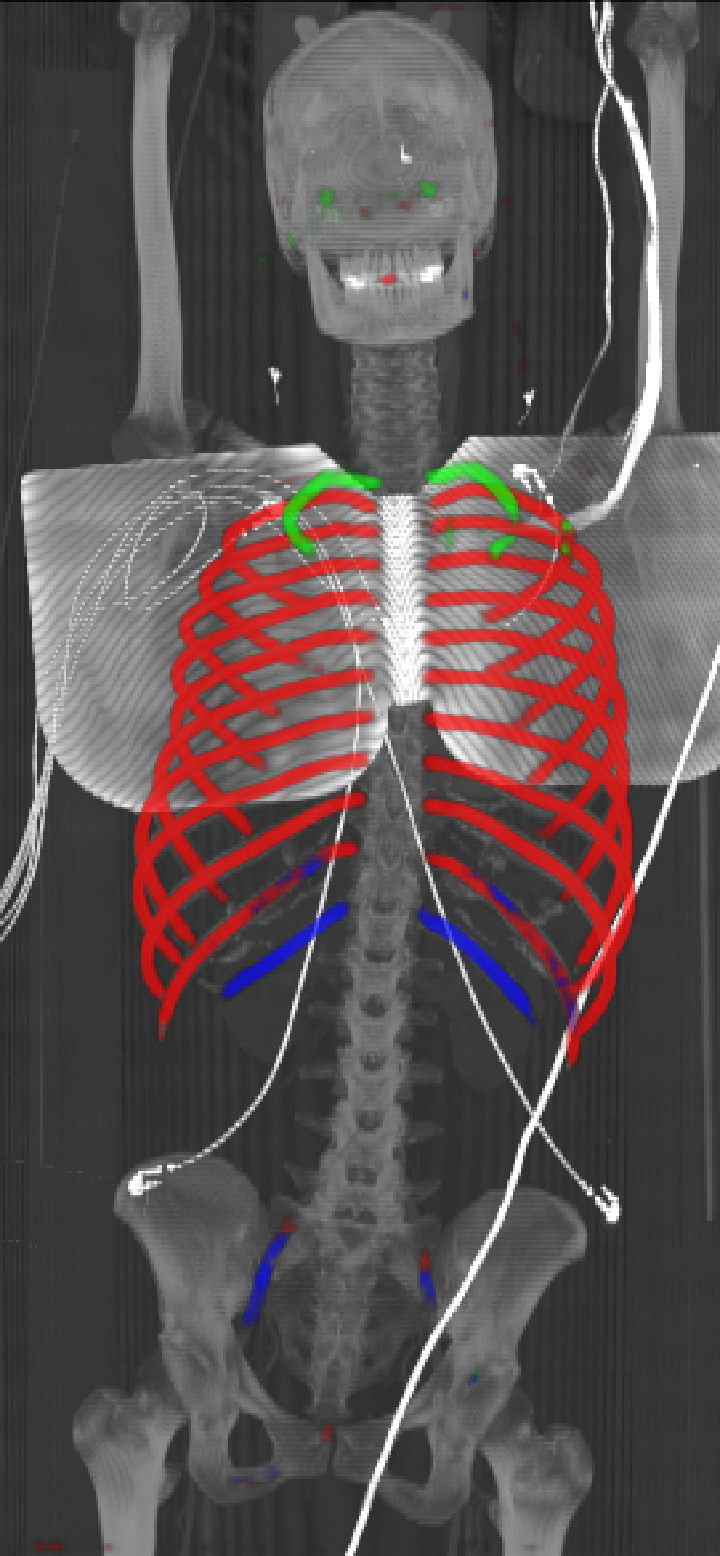

As can be seen from Table 2, we obtain overall good performance for the overall rib detection captured for example with an mean Dice of 0.84. Let us remark that for thin objects, such as the dilated rib centerlines, the Dice score constitutes a rather sensitive measure. The results indicate that detecting the first and twelfth rib pairs is more difficult for our network. While extraction of the first rib is more challenging due to, e.g., higher noise in the upper thorax or other bony structures in close vicinity (clavicle, shoulder blades, vertebrae), the twelfth rib can be extremely short and is easily confused by the neighboring ribs. For further illustration, Figure 4 shows the results on selected representative cases. Generally, the ribs are well detected without major false responses in other structures - despite all the different challenges present in the data. The color coding highlighting of the multi-label detection reveals that first and twelfth are mostly correctly detected. In few cases the network wrongly generated strong responses of the classes first rib or last rib for voxels belonging to the second or eleventh rib pair.

Refer to caption

Figure 4: Maximum intensity projections (MIP) of selected CT volumes overlaid with the multi-label output of the neural network (green: first rib; red: intermediate rib; blue: twelfth rib). The selected case above display common difficulties which are inherent in the data set, such as pads (a) or cables (b), internal devices such as pacemakers (c), stents (d), spinal (e) and femural/humeral implants (f), injected contrast agents (g), patient shape variations such as scoliosis (h), limited field of views (FOVs), i.e. partly missing first (i) or twelfth rib (j).